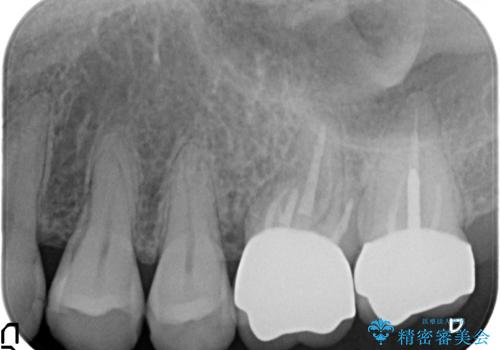

検査の結果左上6に打診痛、根尖部圧痛、根尖病変を認めたため、再根管治療を行ったところ症状が緩解したため、オールセラミッククラウンによる補綴を行いました。

左上7は治療を希望されなかったため、オールセラミッククラウンによる補綴のみを行いました。

- オールセラミッククラウン…¥100,000×2、仮歯…¥10,000×2、ファイバーコア…¥20,000費用は治療当時の料金となります